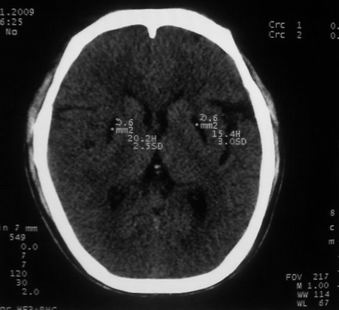

以下是引用随光逐影在2009-1-20 19:38:00的发言:[br]双侧豆状核对称性脑软化灶(中毒性脑病后遗改变?肝豆状核变性?)。

以下是引用jiangjing在2009-1-21 9:38:00的发言:[br]双侧豆状核对称性脑软化灶(中毒性脑病后遗改变?肝豆状核变性?)。